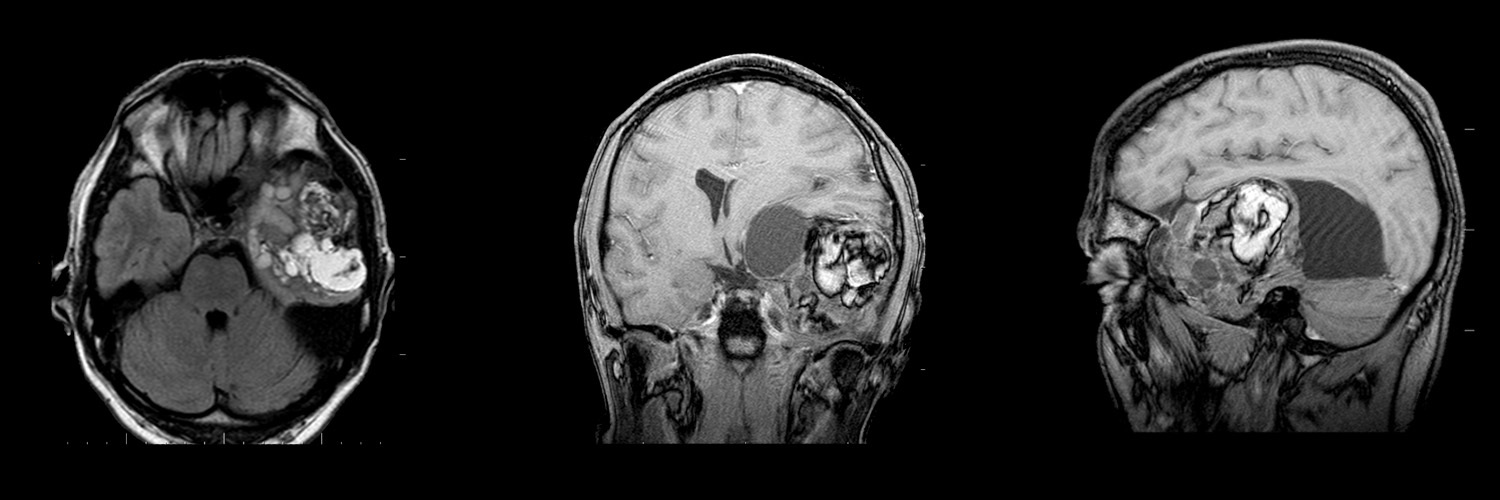

Тератома

Тератома | Портал радиологов